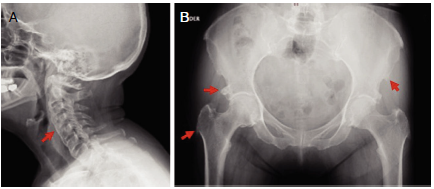

Figura 3 Mujer de 71 años, diabética, con cuadro clínico de 4 años de evolución de dolor y limitación cérvico-dorsal. Hallazgos en la radiografía (A) cervical, puentes óseos C2-C7 (flecha roja), (B) pélvica, excrecencias óseas en entesis de espina ilíaca, acetábulo y trocánter mayor de fémur (flecha roja).